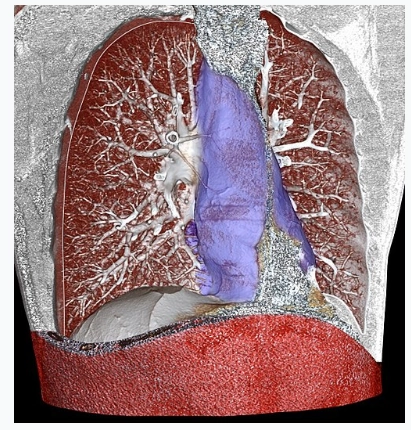

Phình động mạch chủ ngực (Thoracic aortic aneurysm)